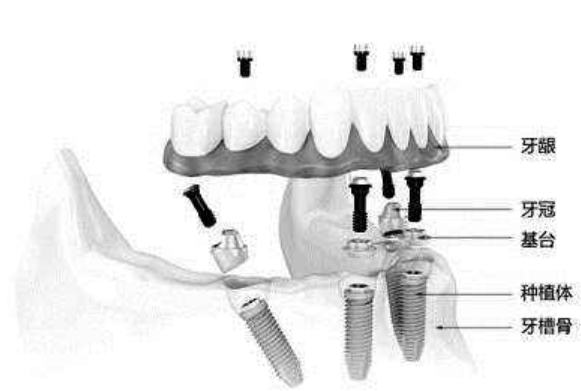

all-on-4技术的核心在于两颗前牙部位的种植体垂直植入牙槽骨内,而两颗中远部位的种植体采取倾斜角度植入牙槽骨内,然后在种植体的基台上安装“拱形连桥”牙冠,这样整个种植牙的受力就呈现出“拱形”的特征,即一点受力会均匀地分布到整体,这在建筑学上是最为稳固的形状。掌握all-on-4即刻种植的机构,在患者口腔状态符合的条件下,大部分都可以实现当天种牙,甚至达到当天戴牙冠吃东西的。》》》推荐阅读:老年人镶牙不容易的原因有哪些?

1. 即刻负重:通过导板种植精准定位,创口极其微小,实现即拔即种,术后即刻恢复咀嚼。

2. 无需植骨:即使在骨量严重萎缩的情况下,也可利用斜行植体等技术,避免植骨手术。

3. 适用范围广:专注解决所有全口、半口无牙颌、牙槽骨严重萎缩/极薄等牙齿缺失问题。

4. 精准快速:仅需要植入传统种植牙一半的植体,对于口腔条件好的患者,种植4颗植体恢复半口牙齿最快仅需1小时。

牙齿种植技术在口腔医学界已经普遍应用,而All-on-4技术可说是业界高端技术。1998年,口腔学生物博士Paulo Malo和他的研究团队历时5年研究,发明了这项只需种入4颗种植体,就可以恢复半口牙的咀嚼功能的技术——“ALL-ON-4”,让您重获自信笑容。